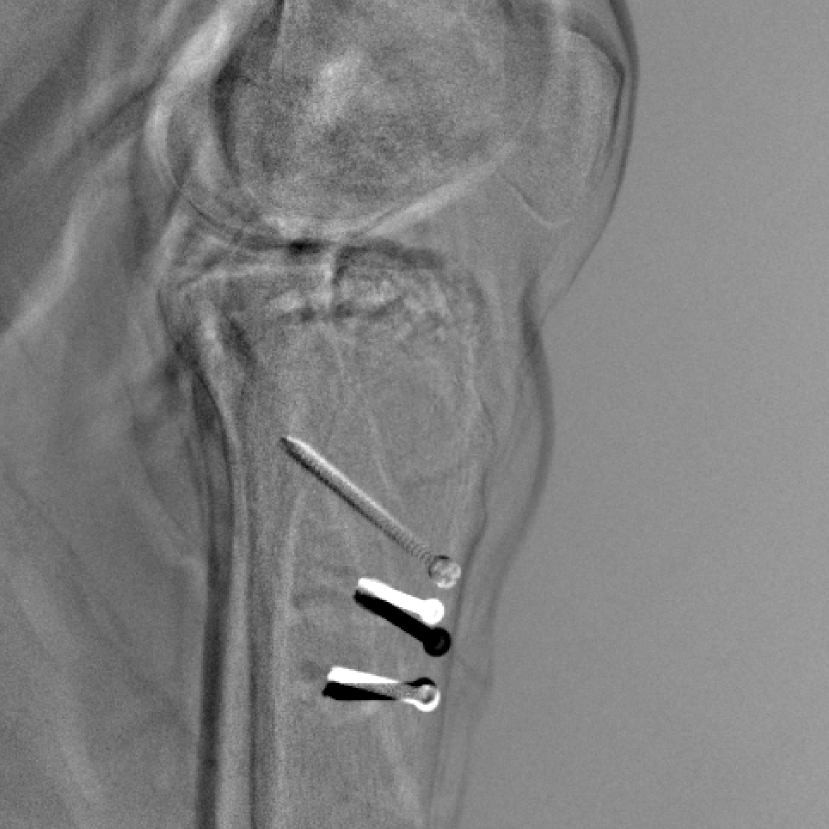

Figure 14: The results for the real cadaver leg data. The green dots mark the positions of landmarks in the corresponding reference images. In the first column, the arrows indicate the bone cavity/fracture structures. In the second column, the solid lines mark the widths and heights of the metals. The green ones are measured from the DRR reference, while the red ones are measured in the corresponding perspective projection image. In the last column, the lines mark the centerlines of the metal screws, where the green lines are those from the reference image. The lengths of the lines in mm are displayed in their corresponding subcaptions. Intensity window: [0, 4]. Please zoom in for better visualization.

The complementary view setting for learning perspective deformation is also evaluated on real CBCT projection data. In this evaluation, real CBCT projection data from a dataset of knees with metal implants is used for testing, while DRRs created from volumetric CT datasets with inserted metals is used for training. Three exemplary DRR perspective projection images for training are displayed in Fig. 13, in which synthetic metal implants are inserted [34]. The appearance, e.g., image contrast and metal image resolution, of such DRR training images is different from that of real projection images in Fig. 14. In Fig. 14, the results for three knees, with and without metal implants, are displayed. The first and second rows are the 0superscript00^{\circ} and 180superscript180180^{\circ} perspective projections, respectively, rebinned to the virtual detector with geometric calibration based on their respective principal points and projections of the world origin. The third row displays their difference images, where the magnitude of deviation increases from the center towards the outside like it does in DRRs with an ideal scan trajectory (e.g., Fig. 6(e)), although real projection data suffer from various physical effects like beam hardening and Poisson noise. The fourth row displays the RGB stacks of 0superscript00^{\circ} and 180superscript180180^{\circ} perspective projection images. The magenta and green regions indicate structures with considerable perspective deformation, for example, the knee patella in Fig. 5.4, the top parts of the two metals in Fig. 5.4, and the bottom two screws in Fig. 5.4. The fifth row displays reference images, which are orthogonal projections of iterative reconstruction volumes from measured CBCT projection data. In the reference images, a total of five landmarks are selected, with the positions being marked by the green dots: In Fig. 5.4, two positions at the edges of the knee patella are marked; In Fig. 14(e) and Fig. 14(f), one position at the left edge of the fibula is marked for each image. In addition, a rectangular frame for the two metals is marked by the green dashed lines, while its width and height are indicated by the green solid lines, which are 29.71 mm and 111.99 mm, respectively. In Fig. 14(f), the centerlines of the bottom two screws are sketched by the green lines, which have the lengths of 17.14 mm (middle screw) and 19.38 mm (bottom screw). The corresponding rectangular frame for the two metals and the screw centerlines in the perspective projection images are marked as well, but in red color. In Fig. 14(a), the width and height of the metals are 32.56 mm and 109.85 mm, which have deviations of 2.84 mm and -1.95 mm to the reference ones, respectively. In Fig. 14(b), the centerline lengths are 18.91 mm and 19.54 mm, which have deviations of 1.77 mm and 0.16 mm, respectively. Although the bottom screw has little length deviation to the reference, the orientations of both screws are obviously deviated. The sixth row shows the results of Pix2pixGAN using 0superscript00^{\circ} and 180superscript180180^{\circ} polar inputs. For all of the landmarks, the green reference dots are all located accurately in the Pix2pixGAN images. The rectangular reference frame also accurately covers the metals in Fig. 14(g). In Fig. 14(h), although the two red centerlines do not exactly overlap with the green one, they are very close in lengths and orientations. Please zoom in for better visualization.